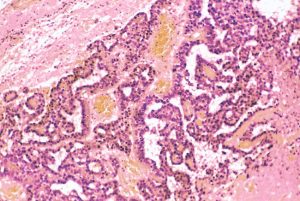

組織学的には,円柱様ないし楕円形の上皮様細胞の網状配列構造を示す腫瘍であり,一部にSchiller-Dubal bodyと呼ばれる血管周囲に集族する特徴的な細胞配列が見られます。これは,一層あるいは多層の上皮様細胞が,中心となる血管をやや離れて取り囲むように並ぶ構造です。また,PAS陽性の好酸性球状体が見られAFPが強陽性となります

視床下部に発生したchoriocarcinomaの病理像(左からHE染色, HCG染色, PLAP染色):腫瘍の大部分にHCG陽性細胞が認められますが,一部ではPLAP陽性のgerminoma細胞様の腫瘍細胞も散見されます。